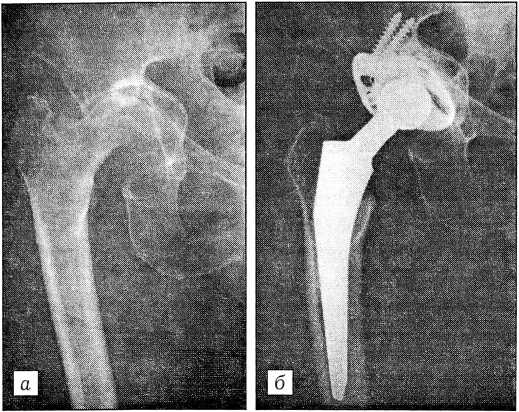

Головку бедренной кости вывихивали в рану и резецировали осцилляторной пилой под углом 45° к оси бедра проксимальнее межвертельной линии. Иногда при протрузии головки или наличии выраженных остеофитов по краям вертлужной впадины вывихнуть головку не удается. В таких случаях мы производили двойную резекцию шейки с удалением участка в 15-20 мм. После отведения бедра головку извлекали из впадины полностью или частями. Фрезами с постепенно увеличивающимся диаметром удаляли остатки хрящевой ткани до субхондральной костной пластинки. После иссечения остатков мягких тканей по периметру вертлужной впадины тестовой чашкой измеряли глубину впадины и определяли ориентиры для установки вертлужного компонента эндопротеза. При использовании цементной фиксации в стенках вертлужной впадины делали 6-10 анкерных отверстий глубиной 10-15 мм, диаметром 6-8 мм. В тех случаях, когда имелись костные дефекты вертлужной впадины (дисплазия, протрузия, кисты, дефекты передней, верхней или задней стенки), производили их пластику аутокостью либо аллокостью из костного банка (135 операций). Кость использовали в виде стружки, пластинок в форме черепицы или отдельных фрагментов. В 78 случаях для укрепления дна и стенок вертлужной впадины были применены металлические кольца Muller и «Beznoska» (рис. 1).

Рис. 1. Рентгенограммы тазобедренного сустава больного ревматоидным артритом с вторичным протрузионным кокситом. а — до операции; б — через 3 года после эндопротезирования эндопротезом Protema-90 («Sulzer») с пластикой дна вертлужной впадины и применением укрепляющего металлического кольца Muller.